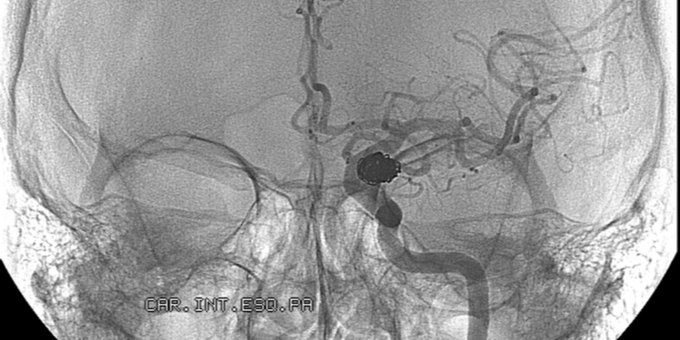

Si las paredes de una arteria cerebral se debilitan, una parte de la pared puede hincharse y formar un aneurisma. En este VIDEO te explicamos qué es un aneurisma cerebral ow.ly/PVwF50yf8GT